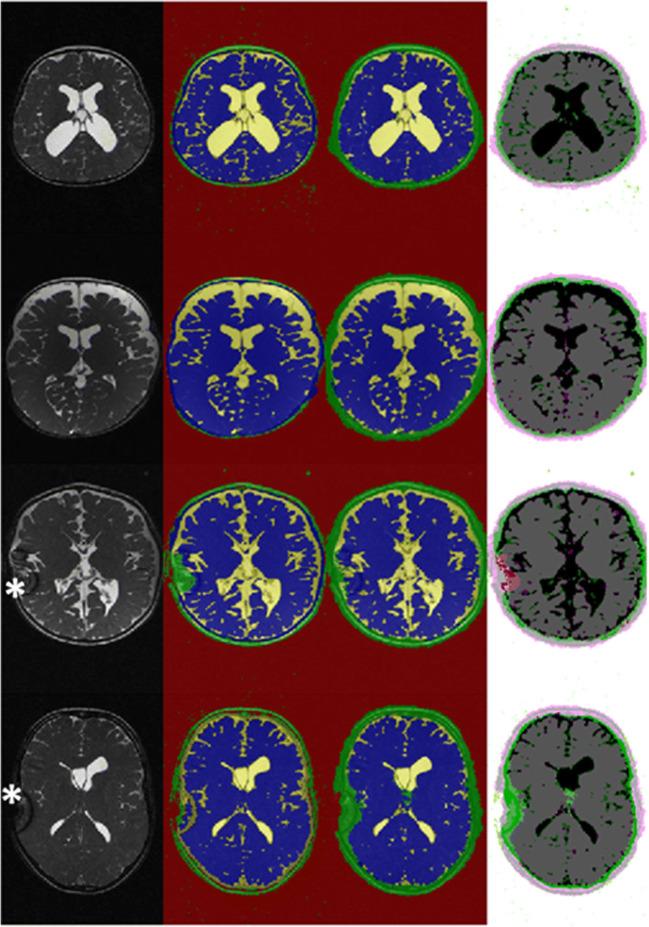

Ninety-five routinely performed true FISP MRI sequences were retrospectively analyzed in 43 patients with pediatric hydrocephalus. Using a freely available and clinically established segmentation algorithm based on a hidden Markov random field model, four classes of segmentation (brain, cerebrospinal fluid (CSF), background, and tissue) were generated. Fifty-nine randomly selected data sets (10,432 slices) were used as a training data set. Images were augmented for contrast, brightness, and random left/right and X/Y translation. A convolutional neural network (CNN) for semantic image segmentation composed of an encoder and corresponding decoder subnetwork was set up. The network was pre-initialized with layers and weights from a pre-trained VGG 16 model. Following the network was trained with the labeled image data set. A validation data set of 18 scans (3289 slices) was used to monitor the performance as the deep CNN trained. The classification results were tested on 18 randomly allocated labeled data sets (3319 slices) and on a T2-weighted BrainWeb data set with known ground truth.

The segmentation of clinical test data provided reliable results (global accuracy 0.90, Dice coefficient 0.86), while the CNN segmentation of data from the BrainWeb data set showed comparable results (global accuracy 0.89, Dice coefficient 0.84). The segmentation of the BrainWeb data set with the classical FAST algorithm produced consistent findings (global accuracy 0.90, Dice coefficient 0.87). Likewise, the area development of brain and CSF in the long-term clinical course of three patients was presented.